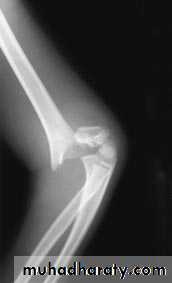

X-ray : the fracture is seen clearly in A-P , and lateral views . In undisplaced fracture the

fat-pad sign which is triangular lucency in front of the distal humerus this will raise the

suspicion of the fracture.

In A-P view we can measure the Boumans’ angle which is helpful in assessing the degree of angulation of the distal segment normally less than 80`.